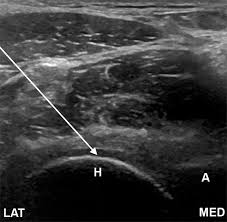

신장(콩팥) 질환

- 신장 결석

- 수신증

- 신장 낭종

- 신세포암